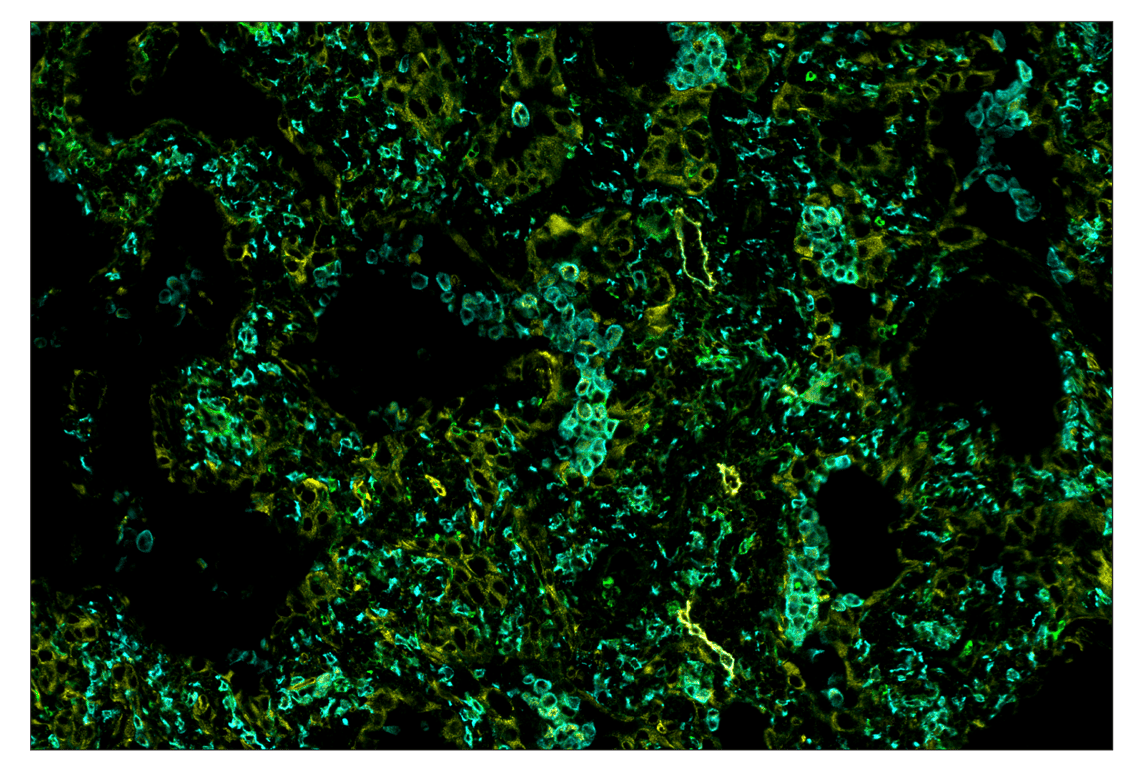

SignalStar™ multiplex immunohistochemical analysis of paraffin-embedded human squamous cell lung carcinoma using CD11b/ITGAM (D6X1N) & CO-0037-488 SignalStar™ Oligo-Antibody Pair #19619 (green), Ki-67 (8D5) & CO-0014-488 SignalStar™ Oligo-Antibody Pair #89034 (cyan), Pan-Keratin (C11) & CO-0003-594 SignalStar™ Oligo-Antibody Pair #30989 (orange), NT5E/CD73 (D7F9A) & CO-0039-647 SignalStar™ Oligo-Antibody Pair #57131 (red), and CD8α (D8A8Y) & CO-0004-647 SignalStar™ Oligo-Antibody Pair #66676 (magenta). All fluorophores have been assigned a pseudocolor, as indicated. Staining was performed on the BOND RX autostainer by Leica Biosystems.

Immunohistochemistry Image 1: CD11b/ITGAM (D6X1N) & CO-0037-647 SignalStar<sup>™</sup> Oligo-Antibody Pair